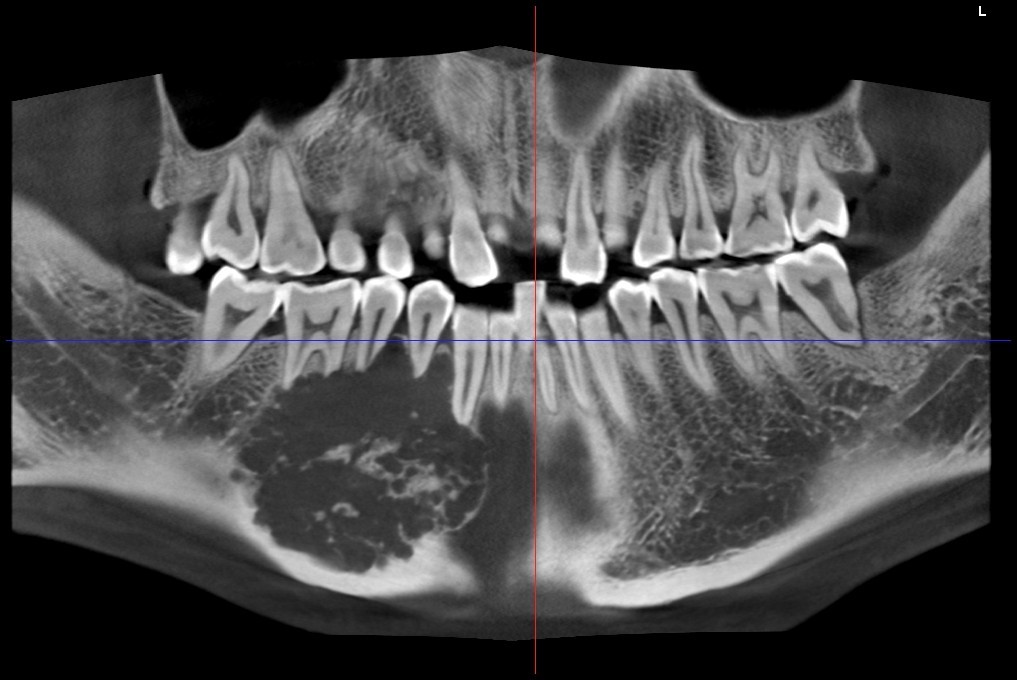

常规开展:数字化根尖片/横断牙合片、数字化口腔曲面体层片、头影测量侧位/正位片、手腕骨片、颅颌面CBCT、牙齿CBCT的检查以及涎腺造影、窦道 瘘管造影。

颅颌面CBCT

诊断范围涉及牙体牙髓病、牙周病、阻生牙/多生牙定位、种植牙术前CT评估分析、颞下颌关节CT诊断分析、,颌骨及涎腺疾病、颌面发育畸形、正畸治疗辅助诊断等大部分颌面部疾病,为临床医疗提供强有力的支持。